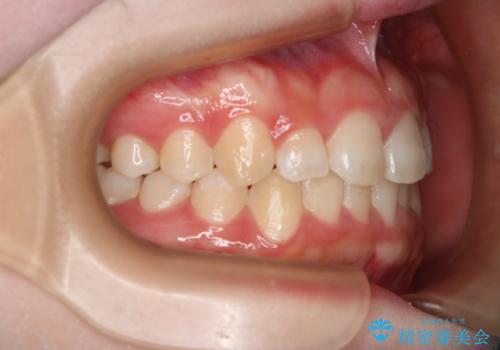

前歯のガタつきを治したい インビザライン・ライトパッケージ

- 前歯のガタつきの改善を主訴に来院された患者様です。

ガタつきによる上顎正中の空隙や歯の突出感も気にされていました。

費用を抑えたいとの事だったので歯の移動量なども考慮し、インビザライン・ライトパッケージでの治療を計画しました。

インビザライン・ライトパッケージでは歯の移動量が限られている分、費用と期間を抑えて治療することが出来ます。